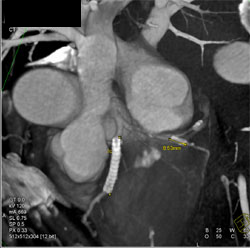

Patent Stent in LAD